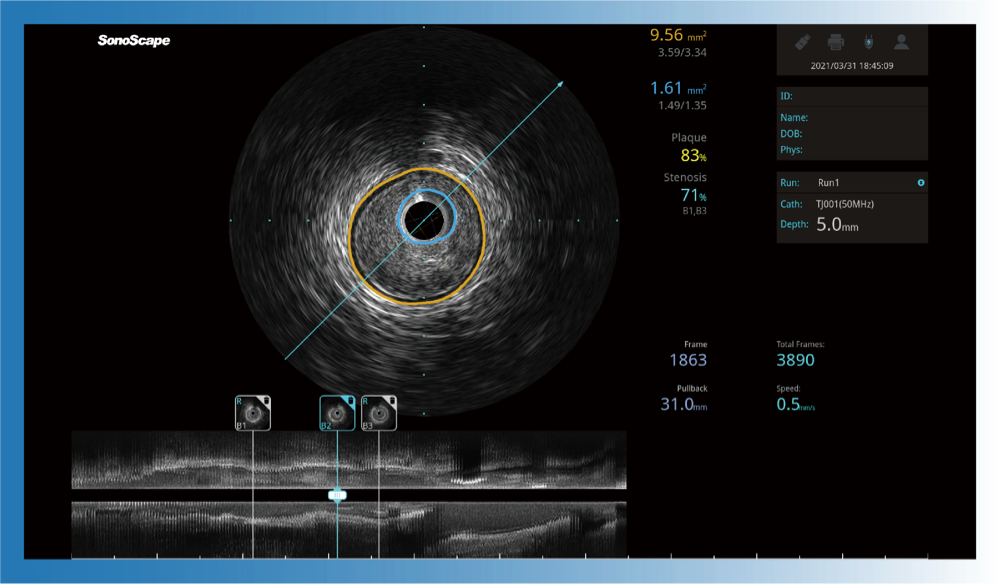

对比传统IVUS导管成像,米兰官方网站宽频IVUS图像的近场支架梁显影更细腻,远场中膜外血管仍清晰可辨,兼顾远中近,兼顾分辨力与穿透深度

一键智能描迹,自动测量斑块负荷、面积狭窄率等指标,准确率高于90%